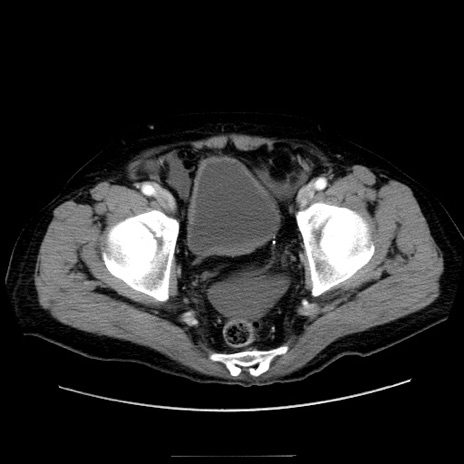

症例30(横断像)

【症例】80歳代男性

【主訴】臍周囲痛

【現病歴】約6時間前から臍下部痛が出現。次第に腹部膨隆・背部痛も生じてきたため来院。背部痛の場所は変化しない。

【身体所見】意識清明、BT 36.3℃、BP  131/87mmHg、P 87bpm、SpO2 100%(RA)、臍周囲自発痛・圧痛あり、反跳痛なし、自発痛部位に一致して板状硬あり、腹部膨隆、腸雑音減弱、CVA tenderness両側陰性。